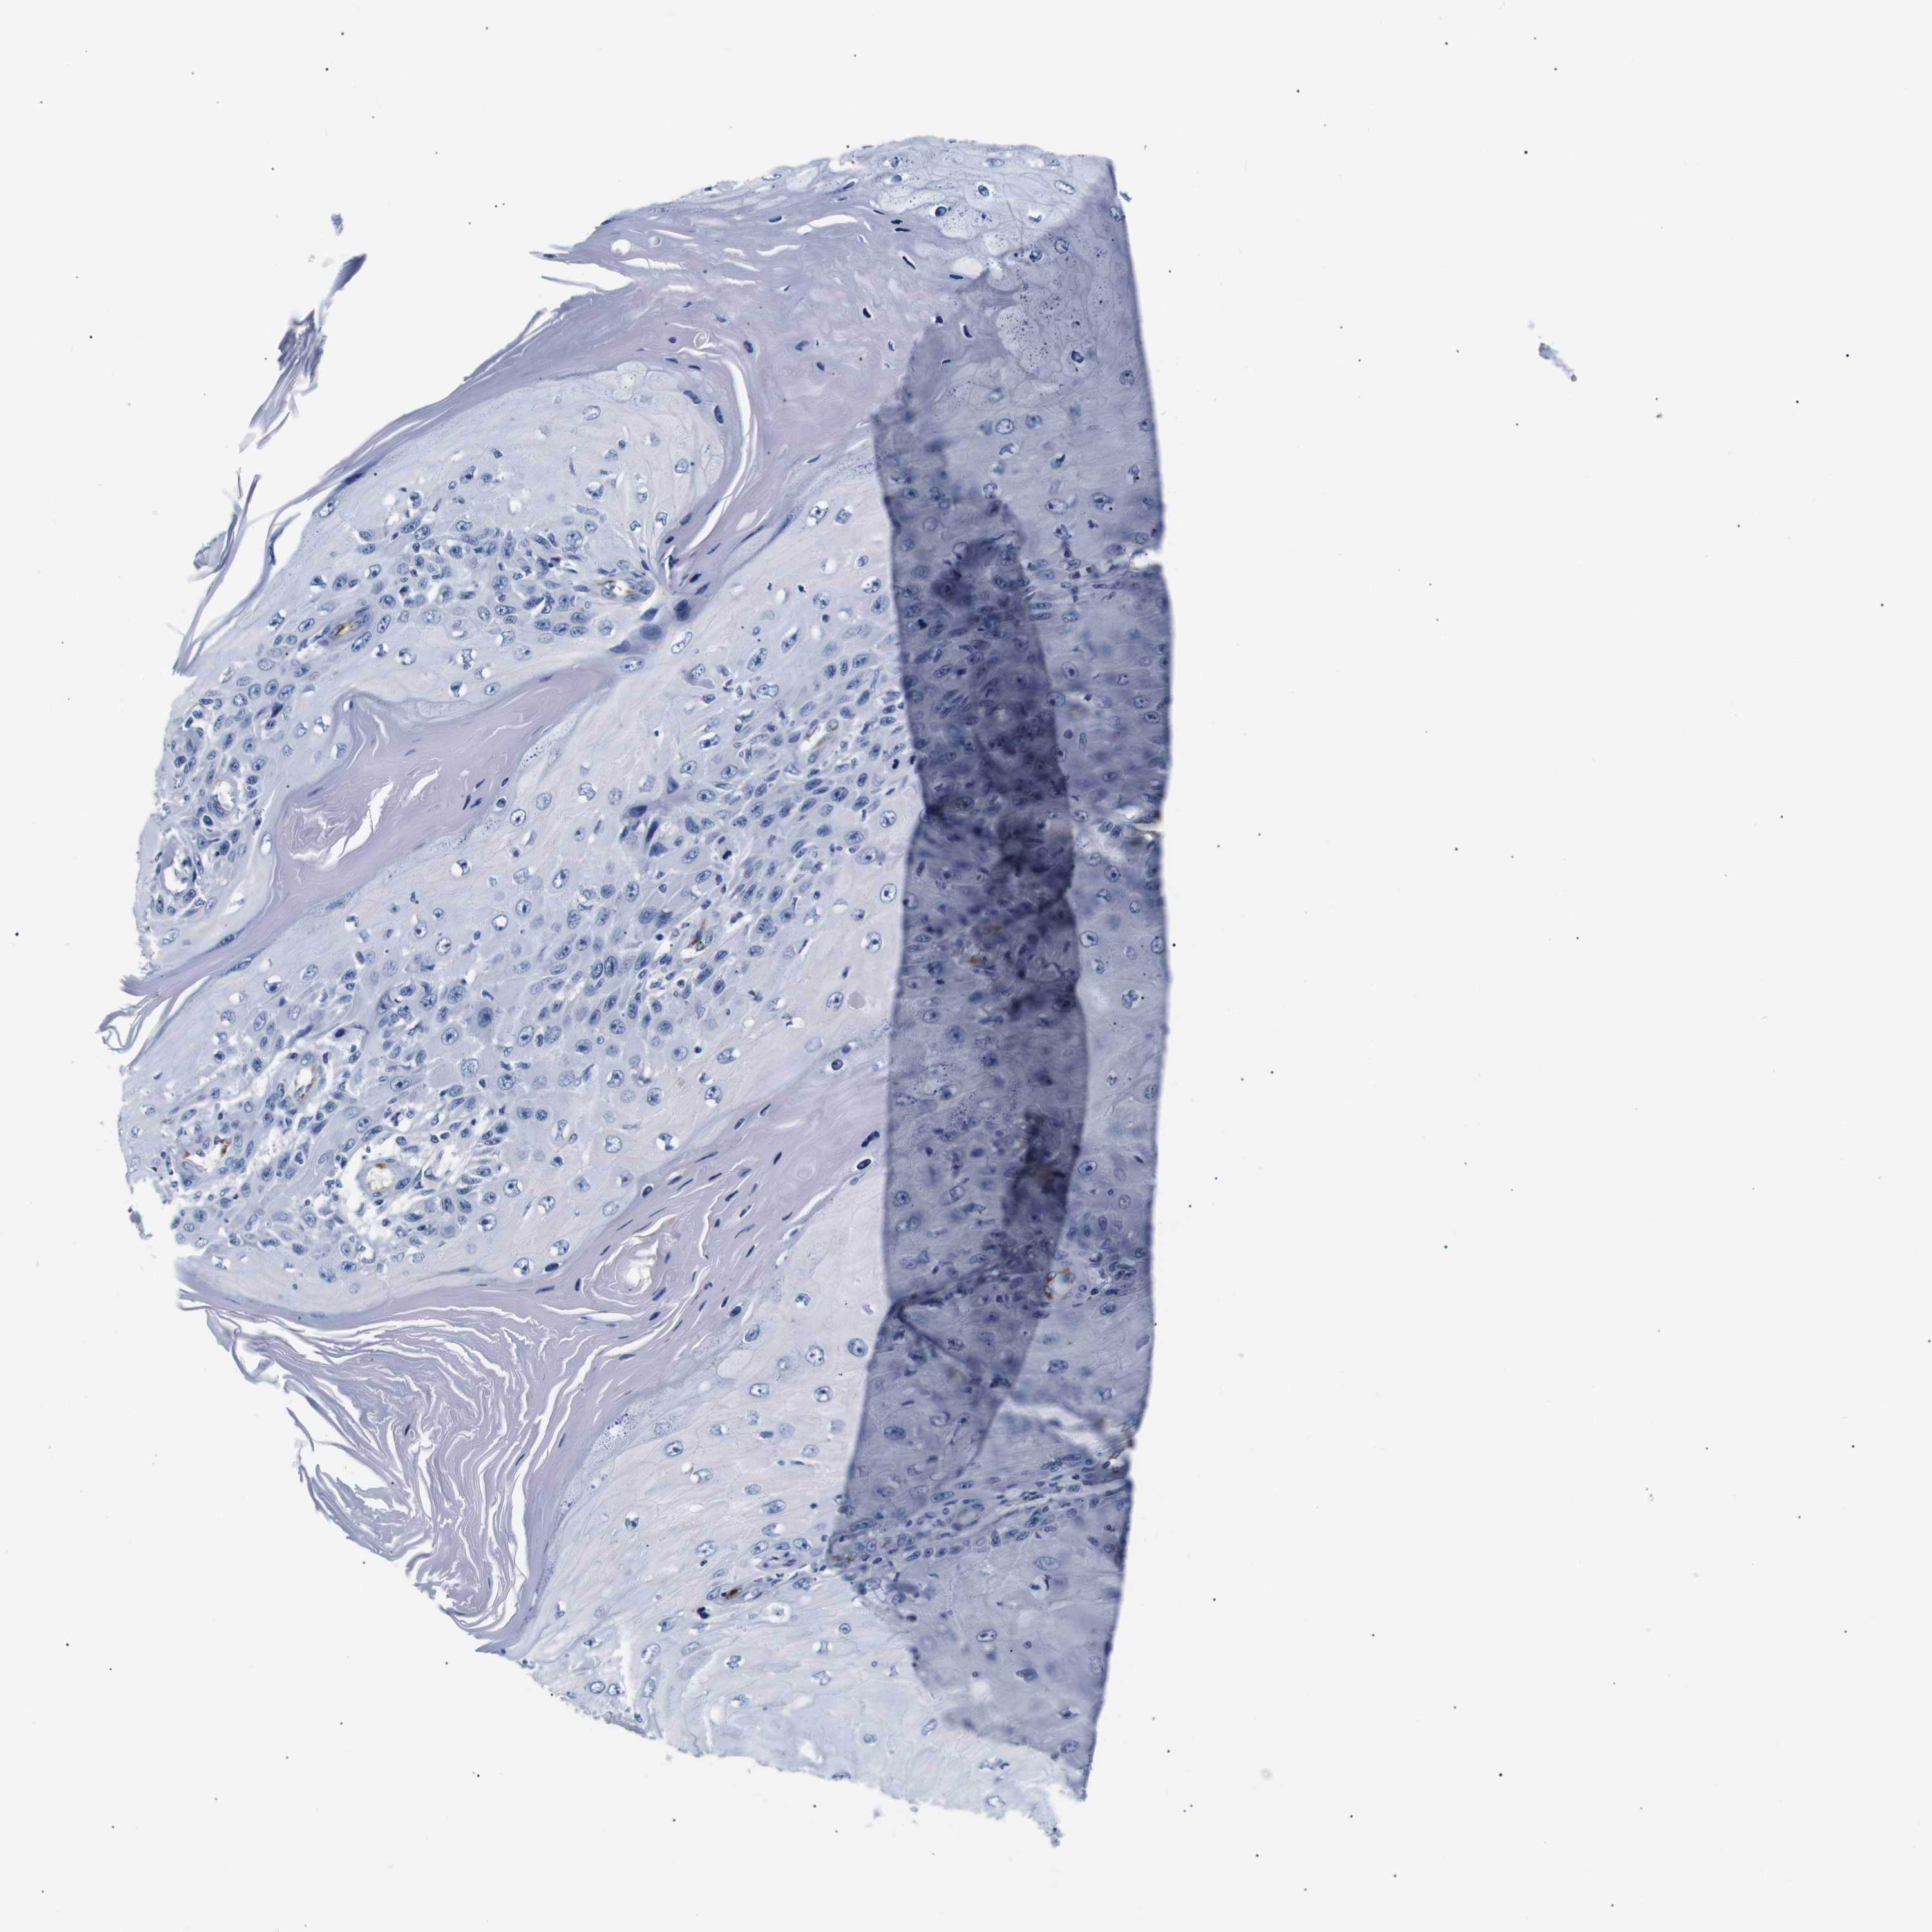

SKIN CANCER - Protein expressioni

A mouse-over function shows sample information and annotation data. Click on an image to view it in a full screen mode. Samples can be filtered based on level of antibody staining by selecting one or several of the following categories: high, medium, low and not detected. The assay and annotation is described here.

Antibody stainingi

Antibody staining in the annotated cell types in the current human tissue is reported as not detected, low, medium, or high, based on conventional immunohistochemistry profiling in selected tissues. This score is based on the combination of the staining intensity and fraction of stained cells.

Each image is clickable and will lead to virtual microscopy that enables deeper exploration of all samples and also displays staining intensity scores, fraction scores and subcellular localization as well as patient and tissue information for each sample.

Antibody HPA005895

Antibody CAB013536

Squamous cell carcinoma, NOS

Basal cell carcinoma